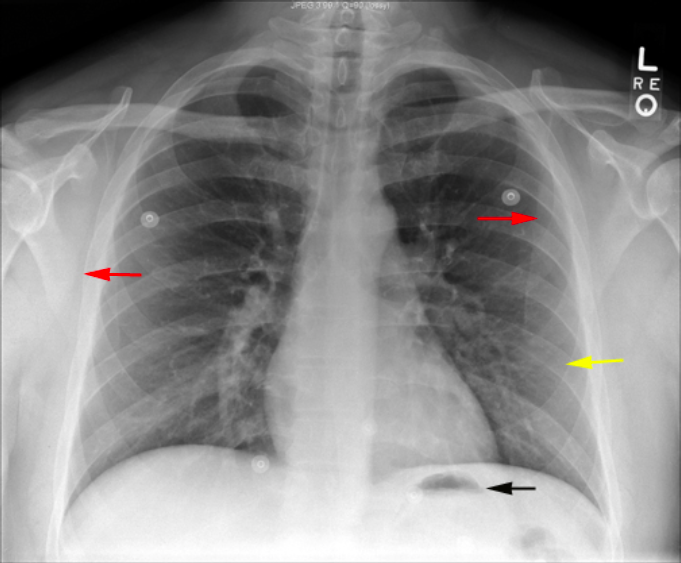

What view is this?

PA View